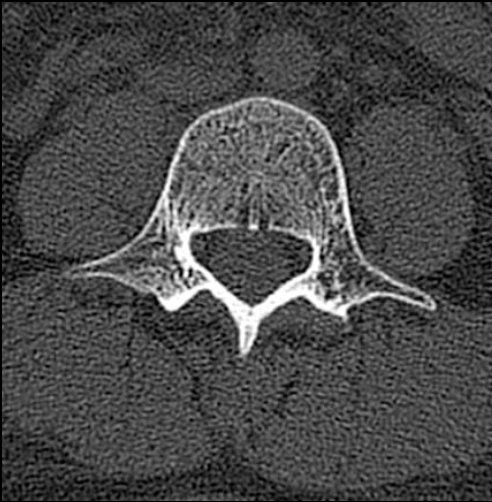

椎体

Vertebral body

椎板

Lamina

关节突关节

Zygapophyseal joint

椎间盘

IVD (Intervertebral Disc)

椎弓根

Pedicle